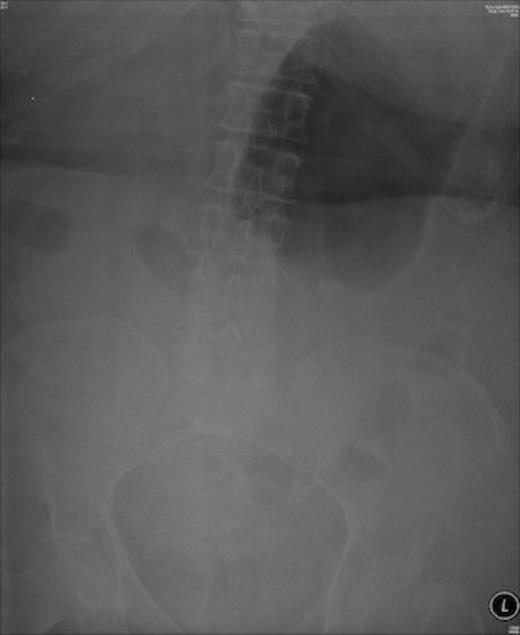

Shortly after admission she suffered an episode of coffee-ground vomiting when her warfarin was stopped and a surgical opinion was sought. Plain x-ray abdomen showed huge gas shadow consistent with gastric outlet obstruction.

Abdominal x-ray showing huge gas shadow consistent with gastric outlet obstruction